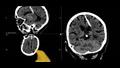

عثر أطباء في منطقة سخالين الروسية على إبرة طولها 3 سنتيمترات، ظلت موجودة داخل دماغ امرأة مسنة طوال 80 عاما، بعد أن توصل الأطباء إلى هذا الاكتشاف غير المتوقع خلال الأشعة المقطعية.

وقالت إدارة الصحة المحلية: "اخترقت الإبرة الفص الجداري الأيسر، لكن لم يكن لها التأثير المقصود، فقد نجت الفتاة".